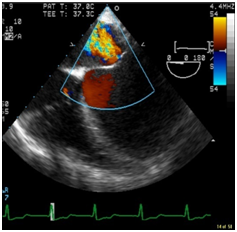

After emptying the stomach, the TEE probe was placed without difficulty. IABP was placed via the right femoral artery. Position of the IABP was confirmed with the TEE. Operation of the IABP was confirmed. A left femoral venous cordis was placed and central access was established. Preoperative TEE found an LV ejection fraction of approximately 5%, severely dilated LV (Figure 1a & Figure 1b), moderately dilated right ventricle, and moderate to severe right ventricular hypokinesis. Patient had a 4+ MR, with significant reversal of the systolic component of the right superior pulmonary venous profile (Figures 1c & Figure 1d).

Figure 1c Color Doppler image of the Mitral valve showing severe Mitral regurgitation (MR).